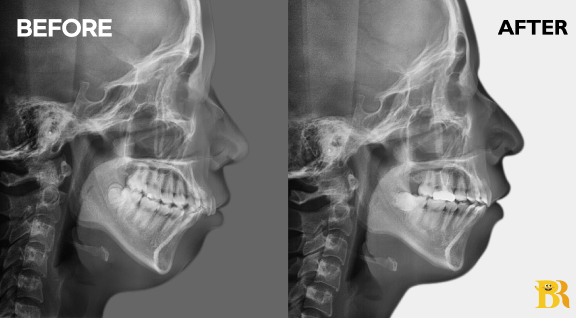

[상악 전치부 매복치를 동반한 케이스] 윗니 2곳에 발치 및 전치부 후방이동으로 돌출입을 해결하고 치열을 고르게 만들었습니다